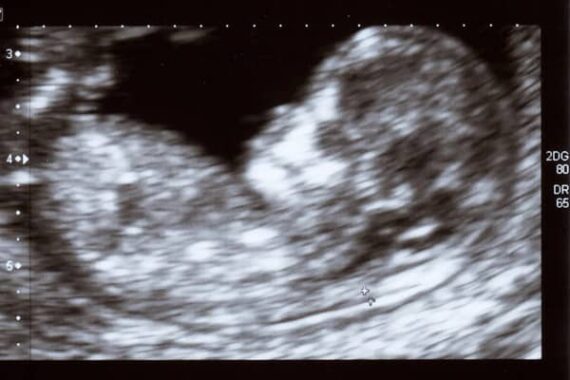

Cette phrase faisait partie du code de déontologie des sages-femmes jusqu’au 31 décembre 2025. Elle a sauté par décret juste avant la fin de l’année, en douce. Aujourd’hui, toute sage-femme est donc tenue de concourir à un avortement si elle est requise ? C’est la fin sans phrase de l’objection de conscience – donc de la conscience. Au cours des dernières années, les sages-femmes ont été autorisées à pratiquer des avortements médicamenteux et des IVG instrumentales.